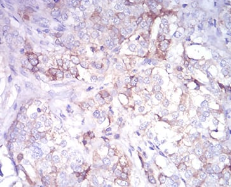

IHC    1/200 - 1/1000